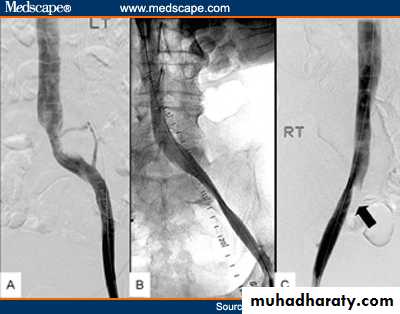

Angiography of iliac vessels